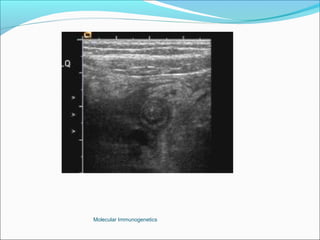

Ultrasound highly sensitive (80-90%), excludes

other pathologies.

The Appendix -Acute Appendicitis Investigations White cell count: high sensitivity 96%, low specificity Urine analysis Plain Xray, nonspecific Ultrasound highly sensitive (80-90%), excludes other pathologies. Computer Tomography: More superior to USS in diagnostic accuracy. Barium enema: Good accuracy, but technically difficult and false positives are common. Laparoscopy Active observation Computer aided diagnosis. Peritoneal lavage Molecular Immunogenetics